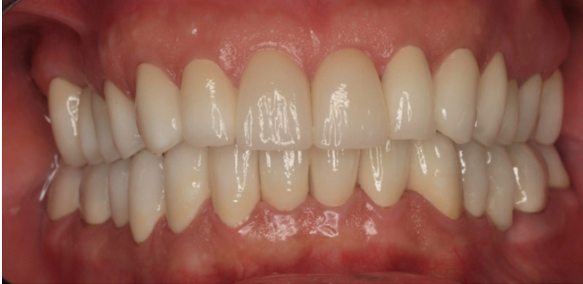

Los brackets de cerámica son dispositivos estéticos, del color del diente que tienen como función acoger un arco para poder enderezar las piezas dentarias mediante fuerzas aplicadas biológicamente al ser adheridos a la superficie dentaria. Son los preferidos por muchas personas, especialmente adultos, que a menudo quieren evitar los aparatos metálicos.

Los brackets de cerámica son mucho menos perceptibles que los aparatos metálicos. De hecho, la mayoría de la gente no los nota, a menos que estén cerca de una persona. Las piezas pequeñas de cerámicas se pegan a cada diente y se coloca un alambre a través de los dientes superiores e inferiores. Estos alambres están hechos de un material compuesto muy fuerte y duradero.